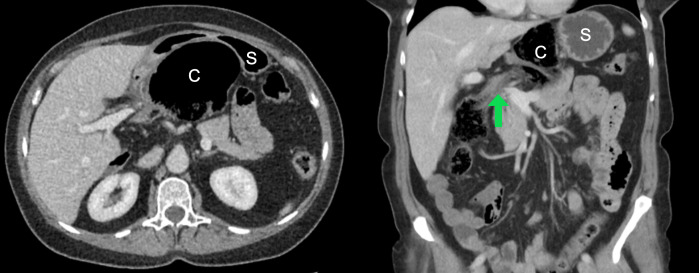

Case presentation: The patient presented with 24 hours of abdominal pain and nausea. Abdominal CT scan revealed a herniated cecum and terminal ileum compressing the gastric chamber and portal vein, leading to periportal edema. Laparoscopic right colectomy was performed after successful colon content evacuation via the greater gastric curvature to facilitate reduction. This was done to aid in reduction, as there were indications of non-viability in the right colon. The procedure unfolded without complications. The patient developed postoperative abdominal collections requiring percutaneous drainage but recovered well and was discharged within two weeks.